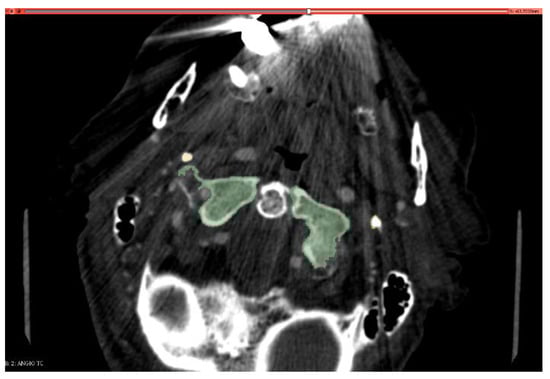

2. Materials and Methods